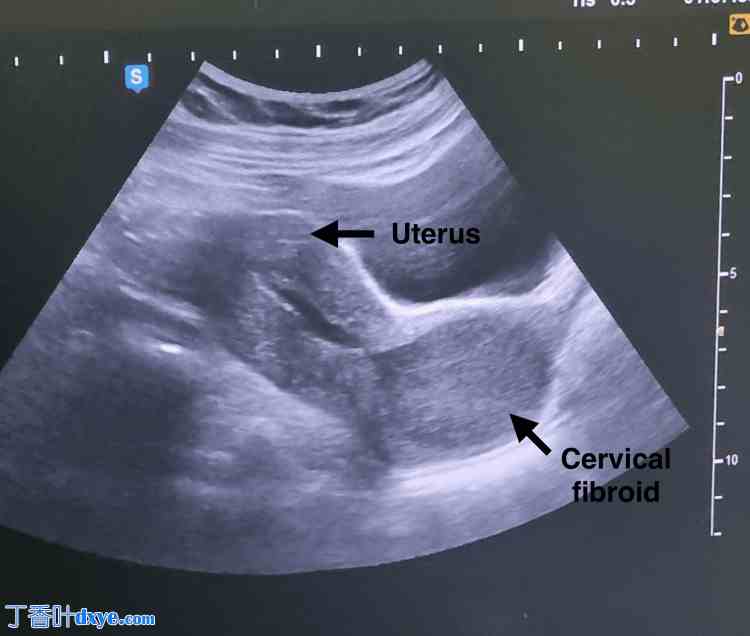

腹部和盆腔增强 CT 显示左侧子宫壁有一巨大肌瘤,延伸至子宫颈区域,大小为 8.4 x 7.3 cm,并伴有双侧多囊卵巢,如图 2 所示。

图 2. 腹部和盆腔增强 CT 显示左侧子宫壁有一宫颈肌瘤,延伸至子宫颈区域,大小为 8.4 x 7.3 cm。